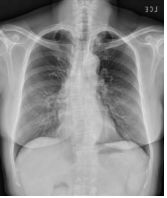

3. This 72-year-old diabetic man was taken to ER for productive cough for 10 days, and rapid progressive dyspnea for 2 days. He also had fever and chill for a week.